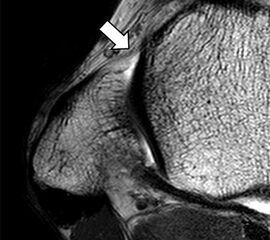

Zu Fehlinterpretationen eines intakten LFTA führt unter Umständen das unmittelbar kaudal des LFTA parallel verlaufende Ligamentum talocalcaneum laterale (Abb. 9 a). Dieses kann bei Verwendung von Schichtdicken um die 3 mm trotz Ruptur des LFTA durch Volumenteileffekte mit Anschnittsphänomenen einen intakten Bandverlauf vortäuschen.

Eine Ursache der falschen Diagnose einer LFTA-Ruptur ist die Fehlinterpretation der physiologische Bandlücke zwischen dem LFTA und der vorderen Syndesmose als traumatischer Banddefekt (Abb. 9 b).

Die Interpretation pathologischer Veränderungen sollte daher immer multiplanar unter Verwendung möglichst dünner Schichtdicken und hoher Ortsauflösungen erfolgen, um Fehldiagnosen zu vermeiden.